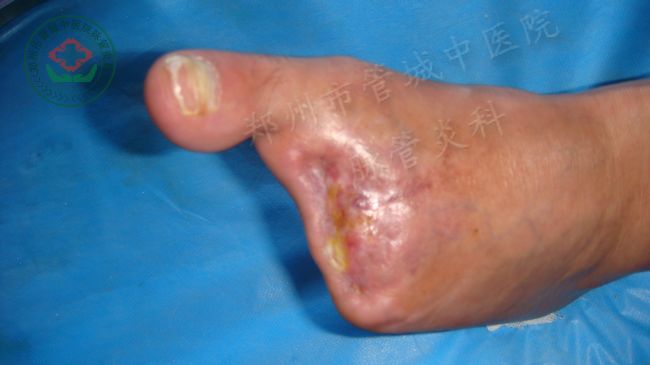

长期医嘱:

通血口服液 40ml tid po

通血康胶囊 6粒 tid po

通血丸 2丸 tid po

外用药:

润肤生肌膏 外涂伤口 一日一次

止痛膏 外涂伤口 一日一次或临时应用

中药医嘱:

中药汤剂 水煎服 早晚两次 温服

消疽散 中药外敷 一日一次

诊疗计划:

1、完善入院相关检查

2、绝对戒烟、戒酒、禁食辛辣刺激食物

3、清热解毒、利湿止痛、活血化瘀类药物应用

4、抗凝、抗感染、改善微循环,对症支持治疗